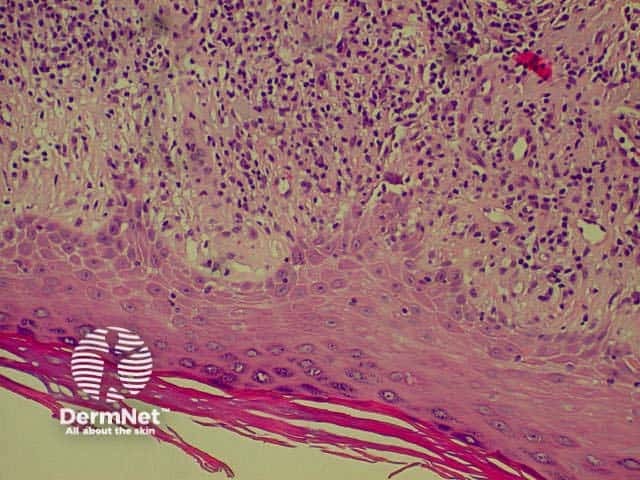

Lichen planus is the idiopathic version of a group of lichenoid disorders characterised by scaling papules or plaques. Link to a clinical description of lichen planus.

The histological features of lichen planus are:

The majority of lymphocytes in the often dense infiltrate are memory cells, identified using histochemistry by positive CD8 and CD45 RO markers.

Direct immunofluorescence nearly always reveals fibrinogen within the colloid bodies. Occasionally IgM and complement are also detected. The immunofluorescence pattern is not diagnostic as the same reactants can also be seen in systemic lupus erythematosus and erythema multiforme.

Lichen planus Lichen planus Lichen planus Lichen planus Lichen planus Lichenoid inflammation